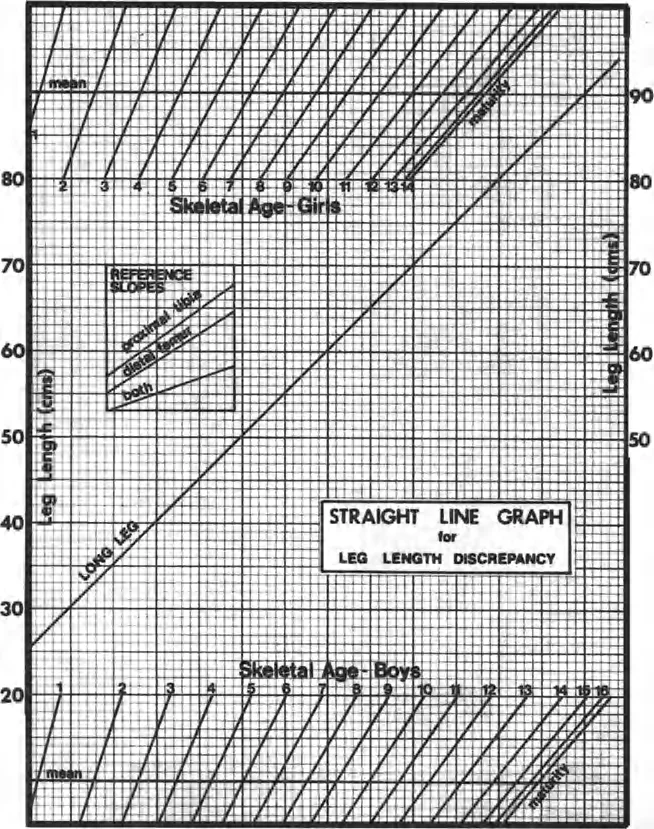

- Obtain Proper Imaging The foundation of planning is a high-quality, standing, full-length AP radiograph of both lower extremities.

- Patella Forward Positioning The radiograph must be taken with the patella facing strictly forward, regardless of foot position. This isolates the frontal plane deformity from any rotational deformity.

- Calibrate the Image Ensure the digital radiograph is calibrated using a scaling marker to allow for accurate millimeter measurements.

- Perform the Malalignment Test Draw the mechanical axis from the center of the femoral head to the center of the ankle. Measure the MAD. Determine if the mechanical axis falls in the medial, lateral, or central zone of the knee.

- Perform the Malorientation Test Draw the individual mechanical axes of the femur and tibia. Measure the mLDFA, MPTA, LPFA, and mLDTA. Compare these to normal values to isolate the source bone of the deformity.

- Locate the CORA Draw the Proximal Mechanical Axis (PMA) and Distal Mechanical Axis (DMA) using the normal joint orientation angles. Mark their intersection as the CORA.

- Select the Osteotomy Rule Determine if the bone can be safely cut at the CORA (Rule 1) or if the cut must be moved to the metaphysis (Rule 2).

- Choose the Osteotomy Sequence Decide between an opening wedge, closing wedge, or dome based on limb length discrepancy and soft tissue constraints.

- Simulate the Correction Using digital templating software, digitally cut the bone, place the ACA, and rotate the segment. Verify that the final mechanical axis passes through the center of the knee and that joint lines are parallel to the floor.